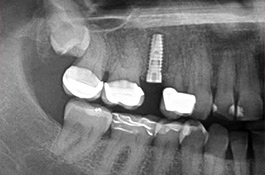

Mittels digitaler Volumentomographie (DVT) sind wir in der Lage, die knöcherne Ausgangslage vor Implantation dreidimensional darzustellen. So können die genauen Lagebeziehungen zu Nerven oder auch zur Kieferhöhle optimal bestimmt werden.